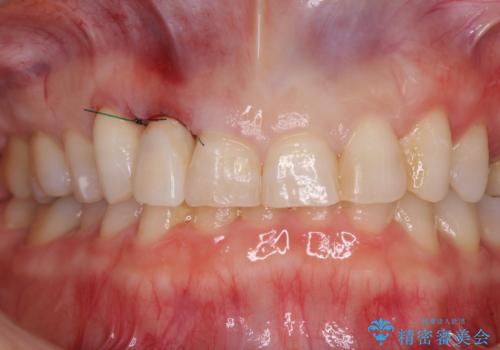

仮歯に置き換えた際に歯周外科処置を行い、歯肉の腫脹が落ち着いたことを確認してオールセラミッククラウンにて補綴することとしました。

外科処置後の痛みを気にしていましたが、小規模の処置であったため、痛みを感じることはほとんどありませんでした。